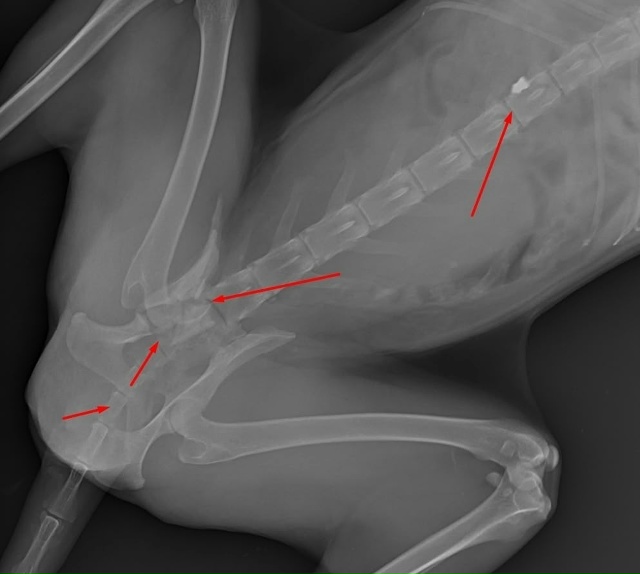

Ветеринары обнаружили у лисы перелом лапы, раздробленный таз, огнестрельное ранение.

Красотке всего 6-7 месяцев, ее нашли в Чусовом с травмами и огнестрельным ранением. Лисе уже сделали операцию и она идет на поправку, однако врачи говорят, что останется небольшая хромота.